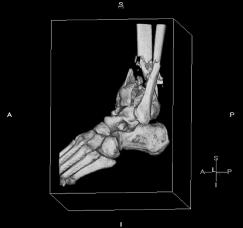

Pre-corrective surgery X-Rays of the damaged right & left legs / ankles

These x-rays were taken at Dr Armendariz’s office, just prior to performing any corrective surgery. As can be seen in these images,

there was no tibia bracing provided by Dr. Keller. Liam was released from Dr Keller’s care with instructions that full weight bearing could

be accomplished within 2 months of Keller’s last surgical procedure. The best example to examine is the second image (from the left) of the

top how. Notice how the bones that should be aligned with the tibia are in fact on the other side of the leg. The third image shows how badly

Liam’s left foot was twisted as a result of the pool placement of the external fixation. What is not obvious is that the screw at the bottom

of the plate on the right fibula missed being screwed into the plate.